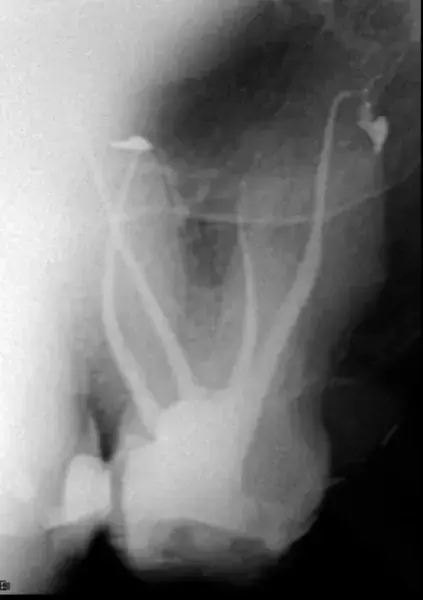

Третият случай подчертава способностите на изкуствения интелект, включен в DTX Studio Clinic, една от функциите на който е автоматичното проследяване на долночелюстния канал. В този случай се оказа много полезна функция. Пациентът е страдал от необратим пулпит на долен мъдрец. Той искаше да спаси зъба на всяка цена, тъй като не искаше да има имплант (моларният зъб е бил опорен зъб за мост). Рентгенографията сочи, че корените на молара се припокриват с канала на долната челюст (фиг. 12). Беше направен 3D скенер и върху него софтуерът проследи долночелюстния канал, който припокриваше молара в панорамния изглед. Ендодонтският режим показа, че каналът заобикаля букалната област, като леко докосва медиобукалния канал (фиг. 13–15). Рентгенографията, направена непосредствено след кореновото лечение, извършено през коронката, показа пълна обтурация на всички канали (фиг. 16)

Фиг. 15 3D реконструкция, показваща, че нервът е заобиколил букалната област и е засегнал само средната част на медиалния канал.